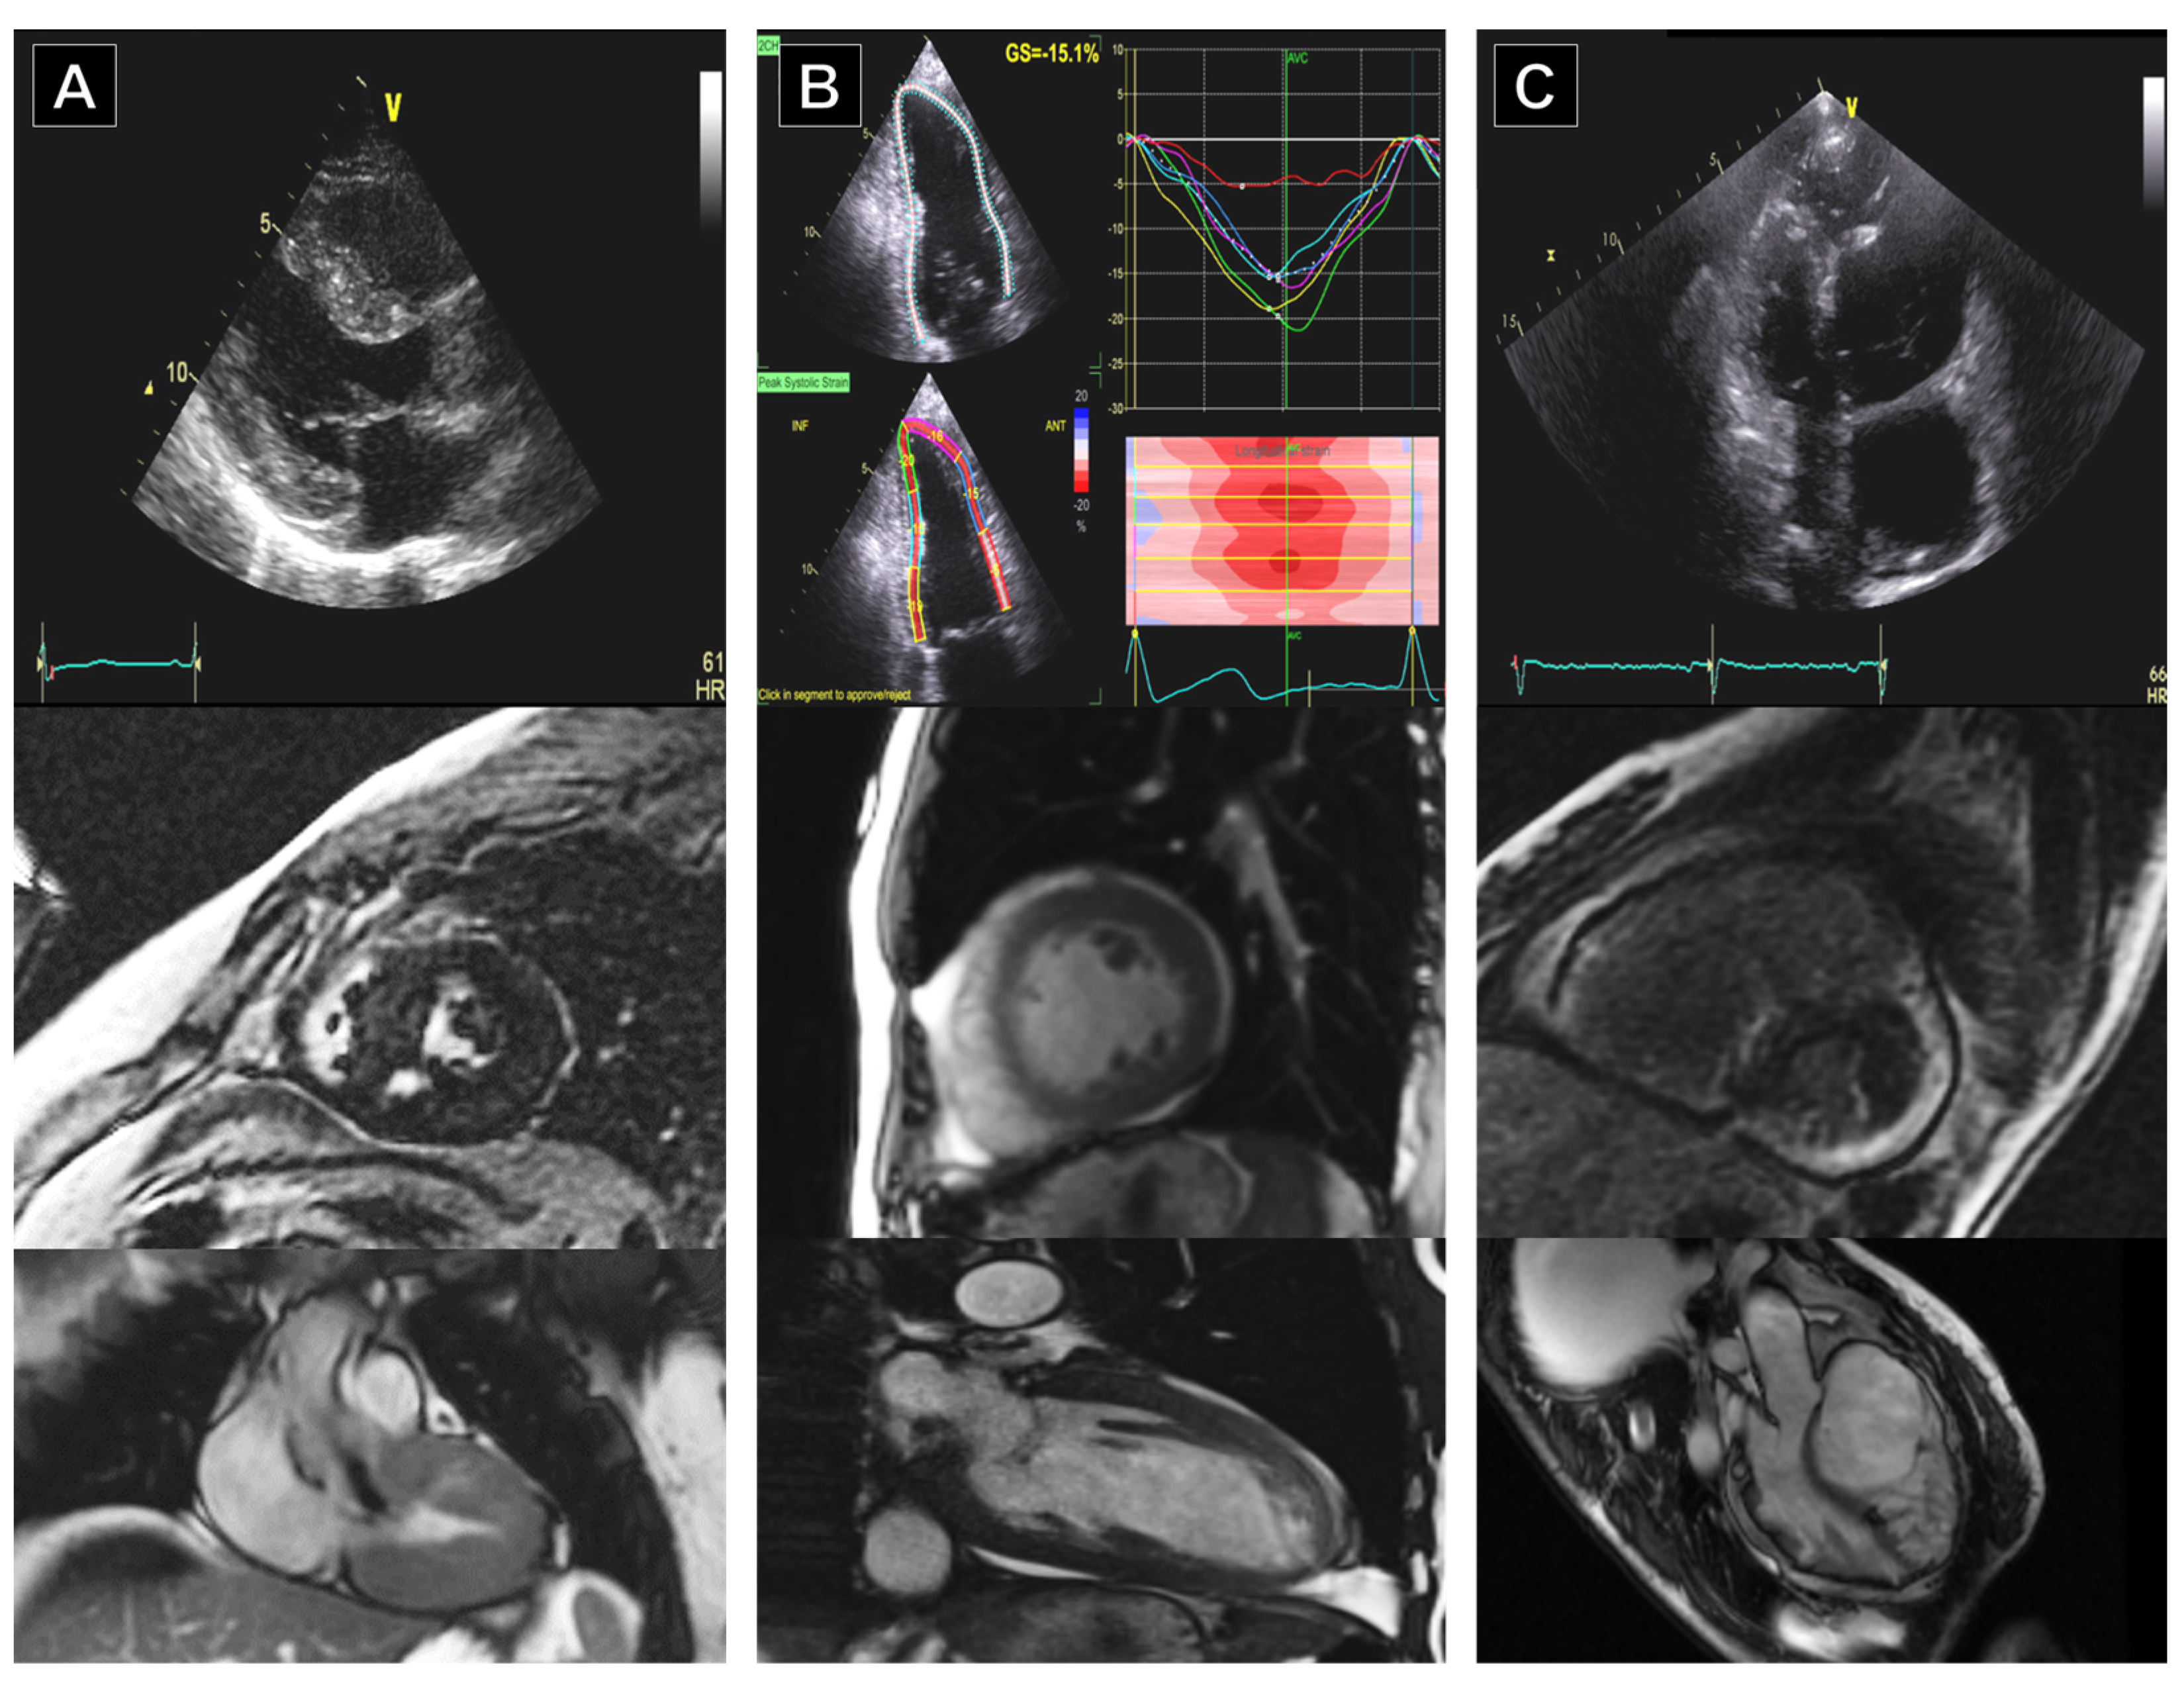

4. Cardiovascular Imaging in Athletes’ Heart

5.1. Dilated Cardiomyopathy (DCM)

5.4. Left Ventricular Non-Compaction (LVNC)